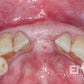

- Defect classification